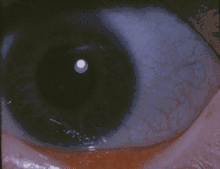

![]() | |

| The classic blue sclerae of a person with osteogenesis imperfecta | |

Osteogenesis imperfecta (OI), also known as brittle bone disease, is a group of genetic disorders that mainly affect the bones.[1][6] It results in bones that break easily.[1] The severity may be mild to severe.[1] Other symptoms may include a blue tinge to the whites of the eye, short height, loose joints, hearing loss, breathing problems and problems with the teeth.[1][4] Complications may include cervical artery dissection and aortic dissection.[7][8]

- Discoloration of the sclera (whites of the eyes), usually giving them a blue-gray color. The blue-gray color of the sclera is due to the underlying choroidal pigment, which shows through. This is due to the sclera being thinner than normal because the defective Type I collagen is not forming correctly.